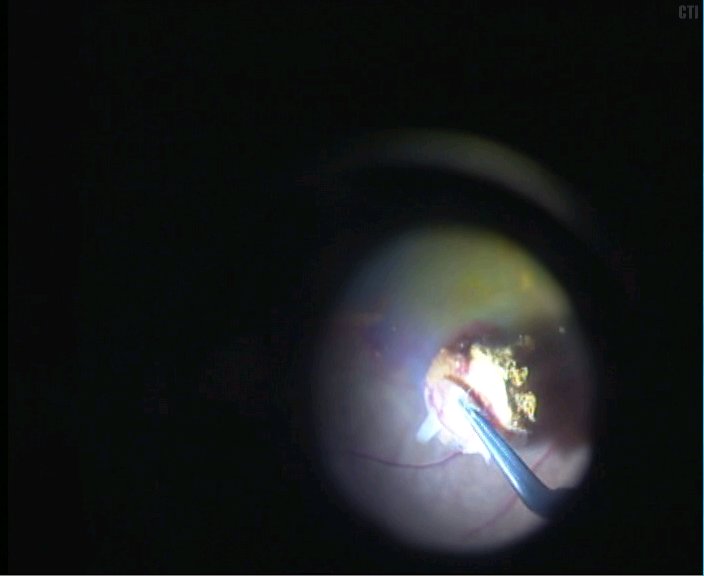

3、局部注水视网膜脱离后取出黄斑下机化的新生血管膜

4、取出机化膜可见黄斑区下大片的色素上皮缺损

5、视乳头鼻上房取1.5PD大小的色素上皮组织

光凝供体区域-切开视网膜-切开色素上皮及其下的部分脉络膜组织-切断游离出色素上皮植片